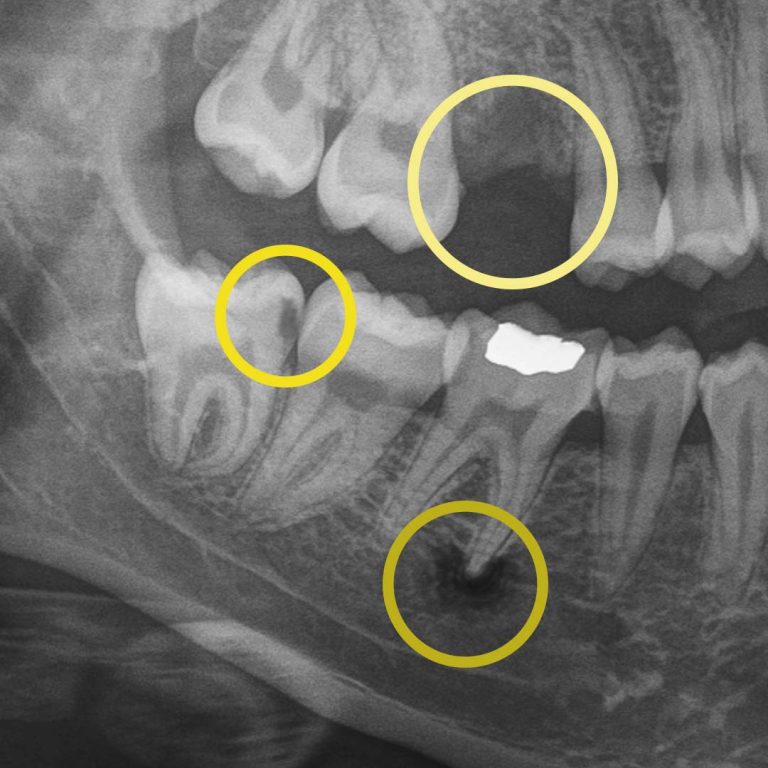

If you’ve ever been told, “Let’s take a quick X-ray,” you might have wondered what your dentist is actually looking for. The truth is, digital X-rays are one of the most powerful preventive tools we use to protect your smile before problems become painful or expensive.

Digital X-rays allow us to see what the human eye simply can’t. They can detect hard and soft tissue changes, and if your dentist uses AI-technology, it can detect changes up to 10x quicker than traditional digital X-rays. More importantly, they help us personalize your care, track your oral health over time, and show you exactly what’s happening, so surprises are limited.

Digital X-rays allow us to look beyond what’s visible. They help us detect:

• cavities between teeth.

• early decay hiding under fillings or crowns.

• bone changes related to gum disease.

• infections at the root of a tooth.

• subtle cracks.

• wear patterns.

• missing primary teeth in children.

For example, during a routine digital X-ray, we may notice a small shadow between two teeth. To the naked eye, everything can look healthy, but that faint shadow often tells us the enamel in that area is starting to weaken. This is considered early-stage tooth decay, sometimes called early “caries.”

Before this decay turns into a hole in the tooth, also known as a “cavity,” we can begin proactive treatment that can prevent the decay from worsening. A prescribed treatment like Curodont™ can repair the tooth (without drilling!) by helping guide minerals back into the enamel and supporting the tooth’s natural ability to heal when it’s paired with good brushing, flossing, and regular professional care. This approach allows us to be non-invasive and protect your natural tooth.

At your next X-ray visit, we’ll compare images to see whether that spot has stabilized or improved. If the area worsens and the enamel breaks down further, a small dental filling may be necessary to prevent deeper decay damaging the tooth structure. If the decay continues unchecked and reaches the inner portion of the tooth where the nerve lives, treatment becomes more complex, often requiring root canal therapy, which can be time-consuming, uncomfortable, and costly.